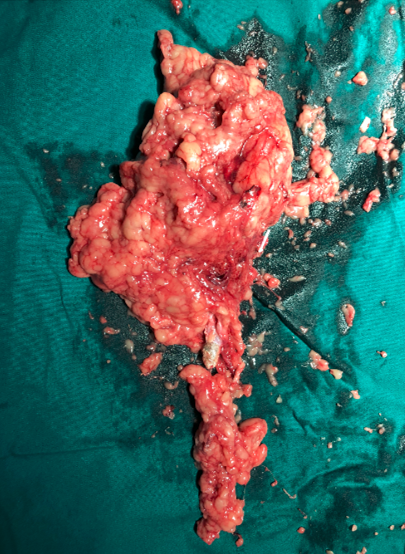

术中完整取出长串的石头

2016年04月手术患者,女性,32岁,昆山人,五年前曾因右输尿管结石引起肾绞痛于当地消炎补液解痉排石处理,疼痛缓解后未于重视,其间从未予复查,2周前出现右腰痛,与当地诊所就诊后予以震波碎石无效,并出现发热,急诊来我院就诊,CT:右肾萎缩,右侧肾脏积水,右侧输尿管多发结石形成石街约4.5*1.5cm,GFR:右侧17.2ml/min,左侧43.2ml/min。因左侧健肾代偿,肾功能正常:Cr 132umol/L;术前诊断:右输尿管下段多发结石 右肾萎缩 肾功能不全,鉴于右输尿管结石梗阻时间太长,肾功能不全,已处于失代偿期,最终也只能行右侧输尿管下段切开取术,解除输尿管下段梗阻,尽可能保护已经萎缩的肾脏,该患者预后不良。